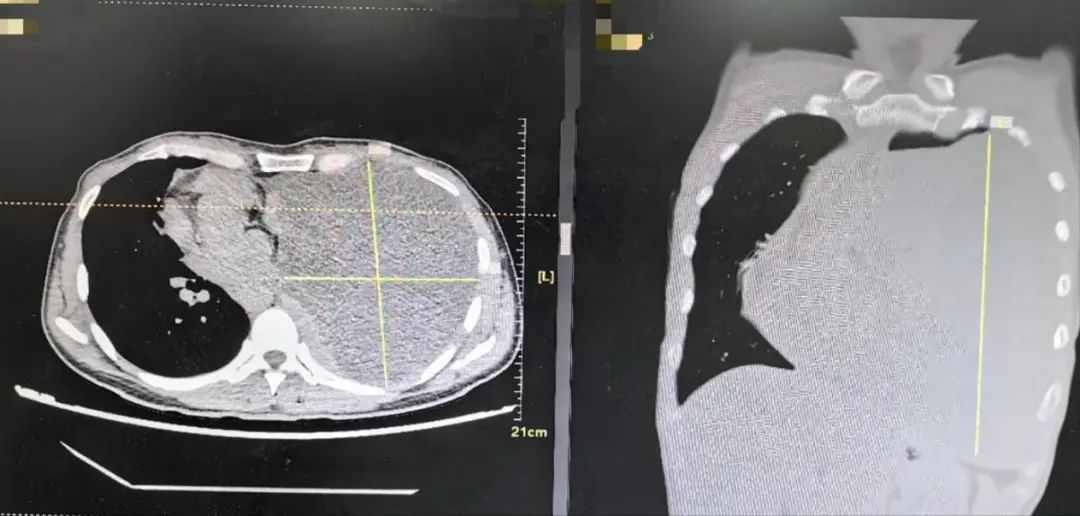

于是,她就诊于福州市第一总医院呼吸与危重症医学科。经肺部CT检查发现:左侧胸腔内巨大占位,几乎占据整个左侧胸腔,心脏气管严重受压移位。

图为影像显示,肿瘤占据了刘女士整个左侧胸腔